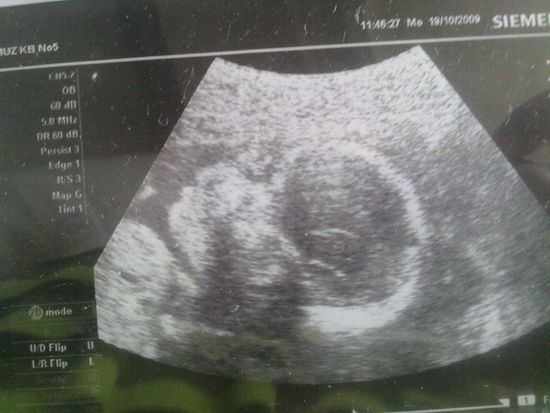

19 октября 2009 года нам было 23 недели,мы пошли на УЗИ и увидели

Муж был в восторге.И еще нам сказали,что у нас будет мальчик,муж в восторге вдвойне.Он очень хотел мальчика(старался видимо и получил).